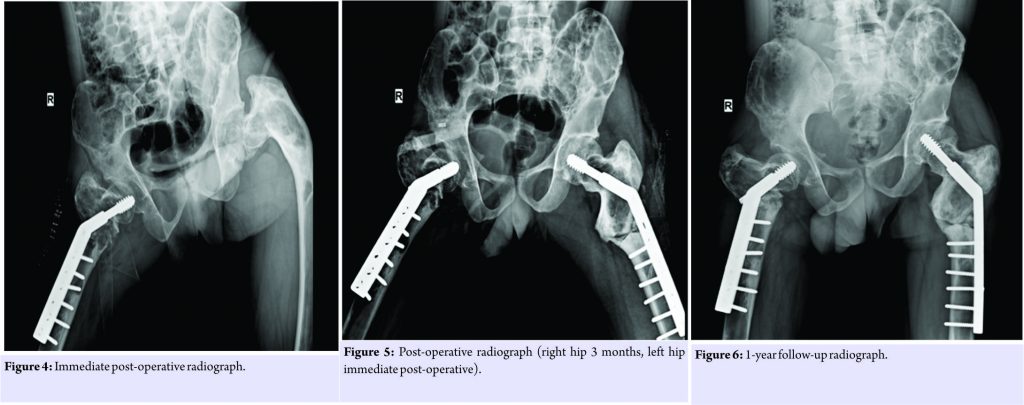

Case Report: A 22-year-old male known case of polyostotic fibrous dysplasia presented with bilateral shepherd’s crook deformity of the proximal femur. Preoperatively, neck-shaft angle was 15° on the right side and 55° on the left side. The patient had severe pain on the right side due to an impending neck of femur fracture. On the right side, we first did a valgus osteotomy in the subtrochanteric region and fixed with dynamic hip screw, and after 3 months, the left proximal femur valgus osteotomy with dynamic hip screw fixation was done. Postoperatively, we achieved a neck-shaft angle of 140° on the right side and 135° on the left side. 1-year follow-up imaging showed union at both the osteotomy sites. At present, at 12-month post-operative, the patient is walking full weight-bearing without support, no apparent shortening.

All the blood and serum biochemical investigations of the patient such as the hemoglobin, total and differential white cell counts, erythrocyte sedimentation rate, C-reactive protein, calcium, phosphorus, and alkaline phosphatase levels, and all the hormonal studies were within normal limits. It was decided to do correction of the deformity to realign the head, neck, and shaft and to achieve valgus at the neck shaft region, in one stage, each side at a time. On the right side, lateral closing wedge osteotomy was done at the subtrochanteric level to achieve alignment of the shaft with the proximal femur and fixed with a 135° dynamic Richard’s screw with a six-holed long side plate. 3 months later on the left side, lateral closing wedge osteotomy was performed at the subtrochanteric level to align the distal shaft with the proximal femur. Fixation was done using a 135° dynamic Richard’s screw with a six-holed long side plate to span osteotomy site. Postoperatively, we achieved a neck-shaft angle of 140° on the right side and 135° on the left side (Fig. 4 and 5). The patient was started on active and passive quadriceps strengthening exercises, and after 6 weeks of immobilization, toe touch weight-bearing was started followed gradually by partial and complete weight-bearing mobilization. Follow-up imaging showed union at both the osteotomy sites bilaterally. At present, at 12-month postoperatively (Fig. 6), the patient is walking full weight-bearing without support and there are no signs of recurrence of lesions of fibrous dysplasia or the deformity (Fig. 7 and 8).